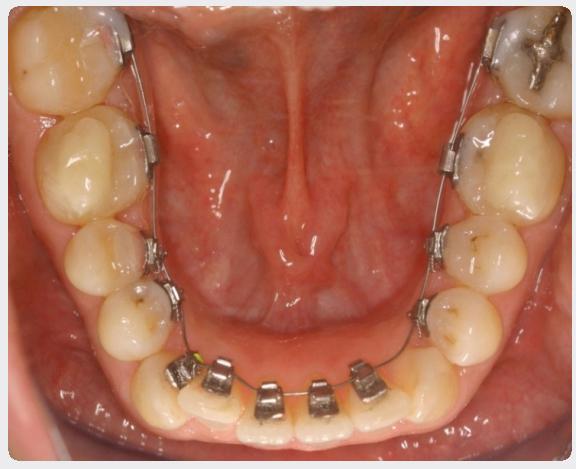

Aparat STb colat pe arcada inferioara

Cu dimensiunile sale reduse si designul deosebit, cu margini rotunjite, noile bracketuri STb sunt concepute pentru a oferi confort maxim pacientului si o intretinere facila a igienei orale. Bracketul STb Light Lingual System are un impact minim asupra poziţiei limbii şi asupra vorbirii; studiile clinice au demonstrat că dificultatile in vorbire sunt neglijabile si dispar în termen de câteva zile de la montare aparatului.